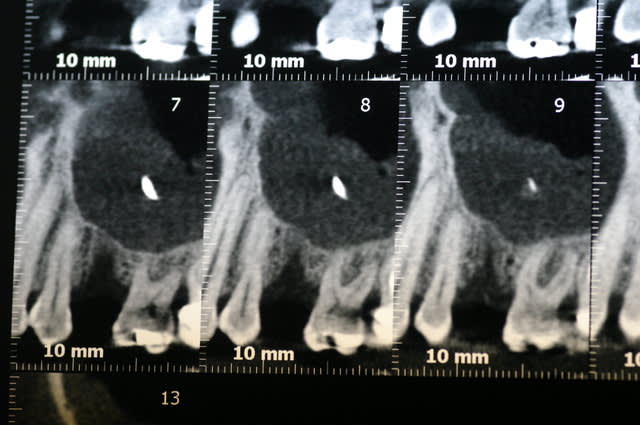

Robin, si tu te sentais prêt pour faire un sinus lift, je te conseille ne ne pas envoyer le patient chez un ORL. L'ORL va faire un Caldwell-Luc avec abord latéral "invasif"qui va compliquer ton traitement futur.

Je te conseille de faire toi même ce curettage où tu préserves le volet osseux d'abord latéral. L'idéal est de réaliser ta fenêtre avec un piezo si tu en as un.

Tu curettes correctement et tu replaces ton volet osseux en l'ancrant avec des sutures résorbables.

Dans 4 mois quand tu y retournes tu auras un sinus parfaitement cicatrisé et l'abord latéral ne sera alors pas compliqué.

Je te poste un cas que j'ai réalisé comment je l'ai décrit çi-dessus.